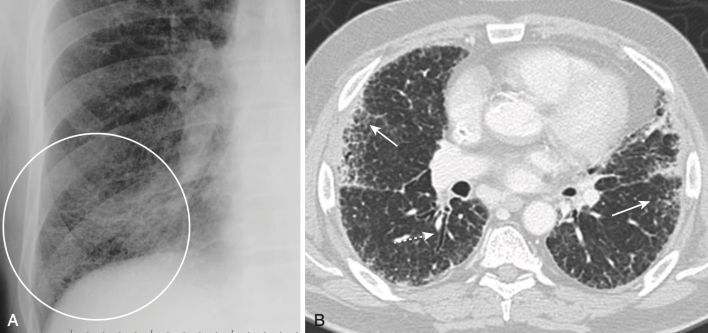

Ung thư biểu mô phế quản (Bronchogenic carcinoma)

- Có bốn loại tế bào chính của ung thư biểu mô phế quản: ung thư biểu mô tuyến, ung thư biểu mô tế bào vảy, ung thư biểu mô tế bào nhỏ và ung thư biểu mô tế bào lớn.

- Đặc biệt, ung thư biểu mô tuyến có thể biểu hiện như một tổn thương dạng nốt phổi ở ngoại vi đơn độc.

- Thông thường, trên phim chụp X quang phổi thông thường, các nốt hoặc khối trong phổi có bờ rõ ràng hơn so với bệnh khoang chứa khí, tạo ra sự phân chia tương đối rõ ràng giữa nốt và mô phổi bình thường xung quanh.

- Chụp CT có thể cho thấy nốt phổi đông cứng hoặc không đều có thể không rõ ràng trên phim chụp X quang thông thường (Hình 13).